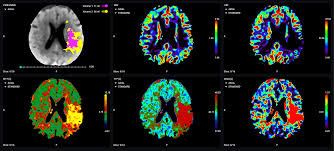

L’analyse de la perfusion cérébrale, réalisée par scanner ou IRM, est enrichie par des logiciels spécialisés (comme OLEA Sphere) qui génèrent des cartes colorées représentant :

- Le débit sanguin cérébral, ou Cerebral Blood Flow (CBF), qui correspond à la quantité de sang circulant dans une région donnée.

- Le volume sanguin cérébral, ou Cerebral Blood Volume (CBV), qui indique la quantité totale de sang présente dans le tissu.

- Le temps de transit moyen et le Tmax qui mesurent le temps nécessaire au sang pour traverser la zone étudiée.

Ces cartes (Figure 5) permettent de différencier le noyau infarci irréversiblement détruit de la pénombre ischémique encore récupérable. Cette approche a fait évoluer la notion de « fenêtre temporelle » vers celle d’horloge tissulaire : ce n’est plus le temps écoulé depuis les symptômes qui guide la décision thérapeutique, mais l’état du tissu cérébral lui-même [27].

Figure 5 : Cartes de perfusion issues d’un scanner de perfusion ou angioscanner (Source : olea medical, 2023) [28]